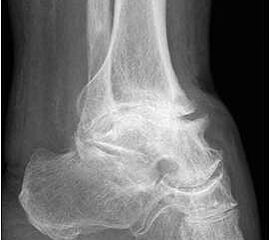

• Primäre oder posttraumatische Arthrose des OSG und USG (Abbildung 1, Abbildung 2).

• Revision einer gescheiterten Fusion des OSG/ USG (Abbildung 3, Abbildung 4).